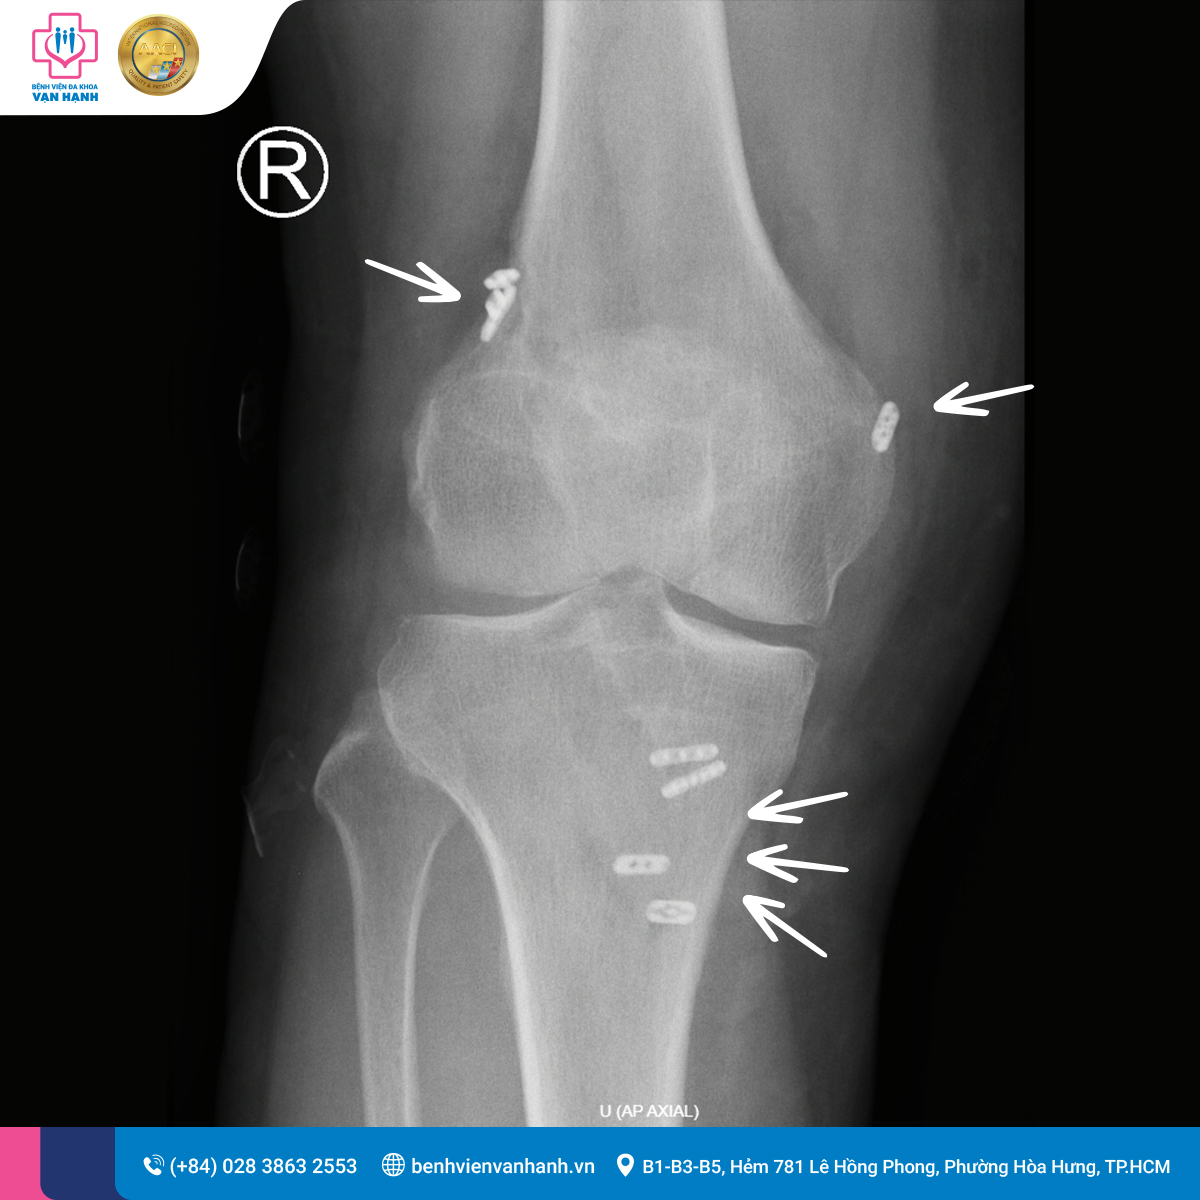

3. Phẫu thuật nội soi tái tạo dây chằng chéo và xử trí rách sụn chêm

Trước tình trạng tổn thương khớp gối phức tạp, các bác sĩ chuyên khoa Chấn thương Chỉnh hình tại Bệnh viện Đa khoa Vạn Hạnh đã chỉ định phẫu thuật nội soi tái tạo đồng thời dây chằng chéo trước, dây chằng chéo sau kết hợp xử trí rách sụn chêm.

Phẫu thuật được thực hiện bằng kỹ thuật nội soi xâm lấn tối thiểu thông qua các đường rạch da nhỏ. Trong quá trình can thiệp:

- Các dây chằng chéo bị đứt, mất chức năng được loại bỏ.

- Được thay thế bằng dây chằng nhân tạo, giúp phục hồi độ vững cơ học của khớp gối.

- Tổn thương rách sụn chêm được cắt lọc – tạo hình theo nguyên tắc bảo tồn tối đa cấu trúc đệm khớp.

Dây chằng chéo nhân tạo được cố định ở khớp gối